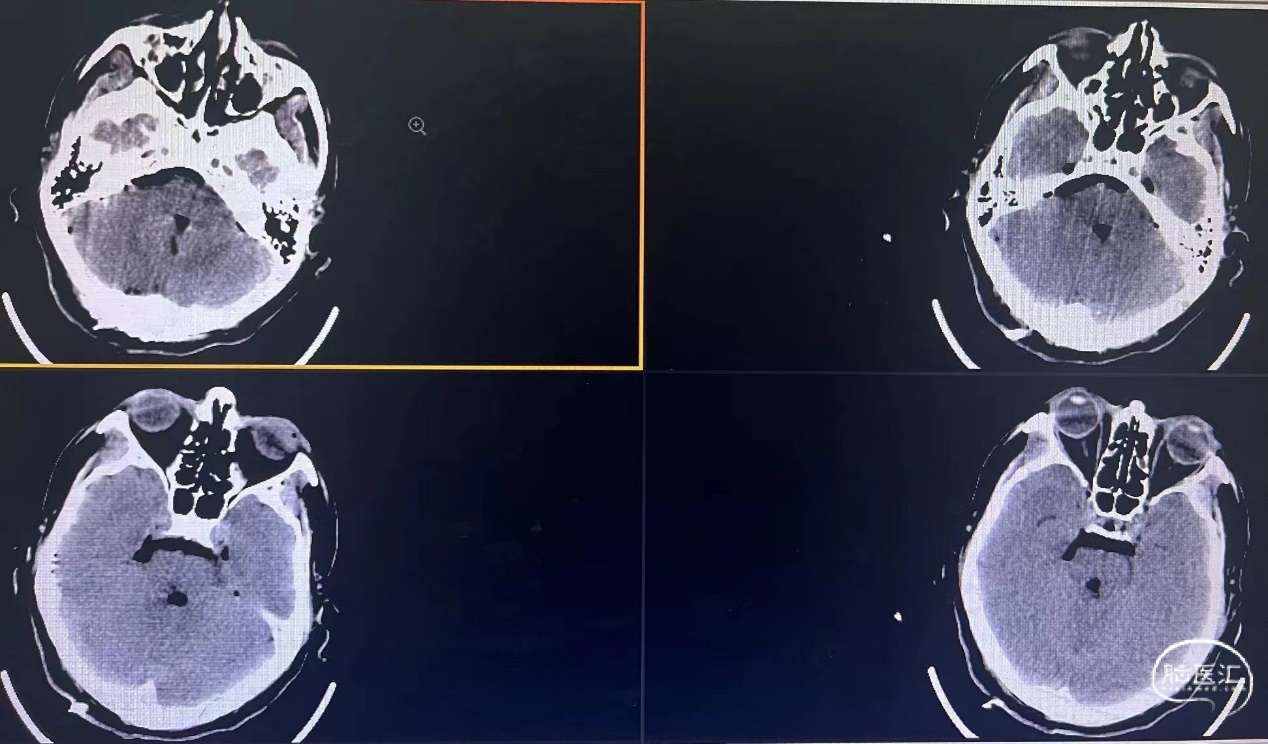

病例一

男,53岁,行走不稳、视物重影6天 BSCMs评分2。

查体:右眼球内收障碍,右侧额纹变浅,右侧额部感觉下降,双侧面部麻木。